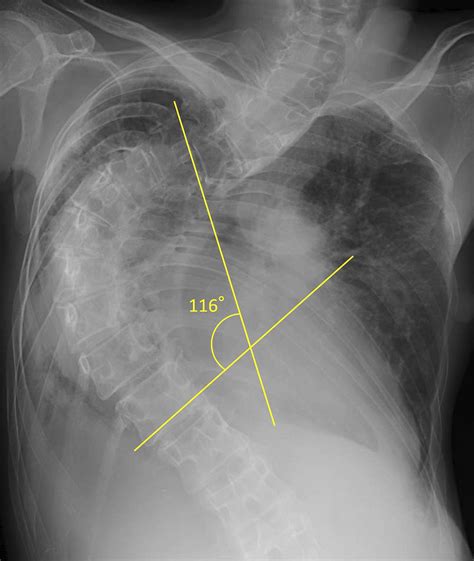

Measuring the Angle of Cobb

Measuring the Angle of Cobb involves several steps, typically performed using X-ray images. Here is a detailed guide on how to measure the Angle of Cobb:

1. Obtain a standing posteroanterior (PA) X-ray of the spine.

2. Identify the most tilted vertebrae above and below the apex of the curve.

3. Draw a line along the endplate of the most tilted vertebra above the apex.

4. Draw a line along the endplate of the most tilted vertebra below the apex.

5. Draw perpendicular lines to these endplate lines.

6. Measure the angle formed by the intersection of the perpendicular lines.

This angle is the Angle of Cobb and represents the degree of spinal curvature.

Interpreting the Angle of Cobb

The Angle of Cobb is interpreted based on the following categories:

Angle of Cobb Severity Treatment Options

10° or less Mild Observation and monitoring

11° to 25° Moderate Bracing and physical therapy

26° to 40° Severe Bracing and possible surgery

41° or more Very Severe Surgery

These categories help guide treatment decisions, with milder curvatures often managed through observation and physical therapy, while more severe cases may require surgical intervention.